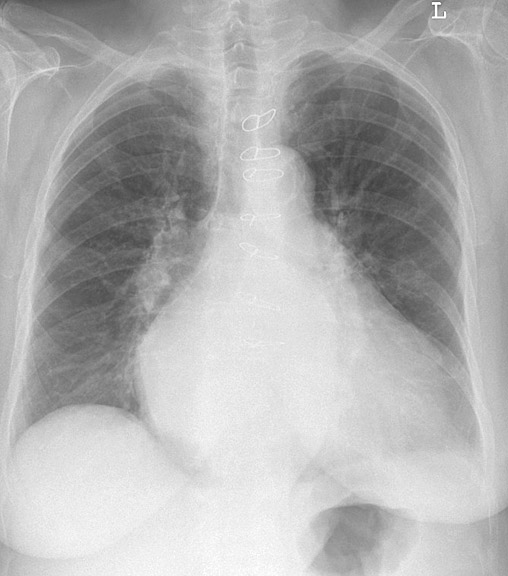

Gallery Cardiac Mitral Valve Disease Mitral Valve Disease Case 4 PA

Mitral Valve Disease

Case 4 PA